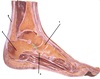

3

4

5

Perfectly

9

Q

S1 nerve root compression

A